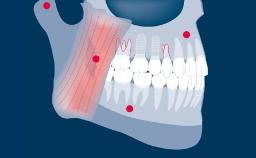

Prosthodontic Planning and Procedures

Design Principles for Combining Single Unsplinted Dental Implants and Partial Removable Dental Prostheses (RDPs)

Learning Module